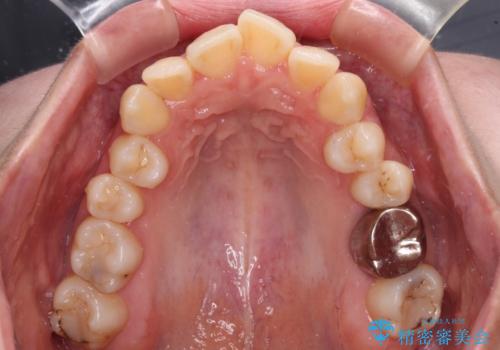

3. 【モニター】急速拡大装置 狭い歯列を拡大してワイヤー装置で短期間治療の治療後